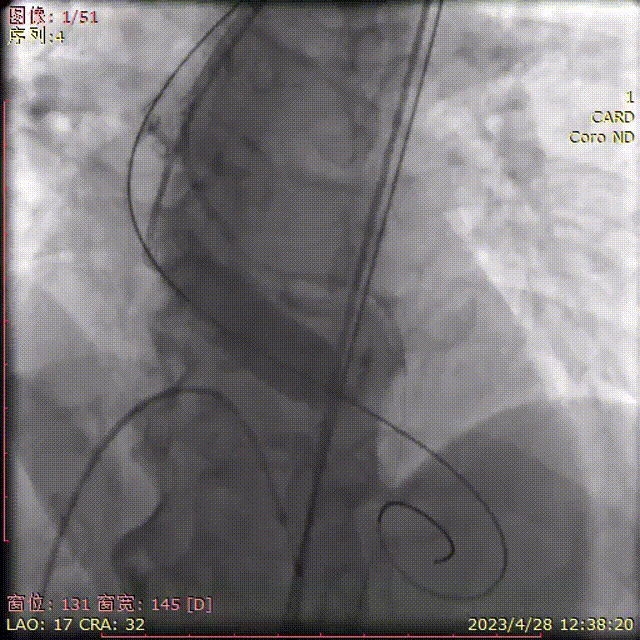

主动脉根部造影

球囊预扩左冠显影良好